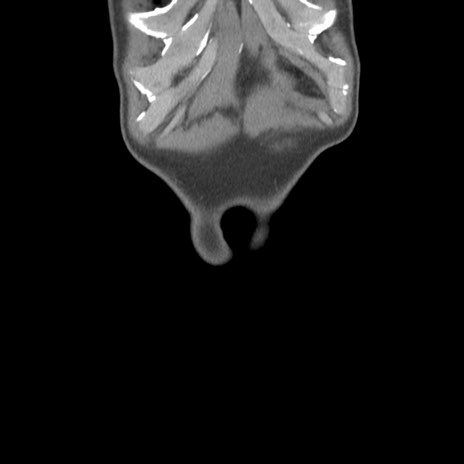

症例56 CT(冠状断像)

脂肪ウインドウ